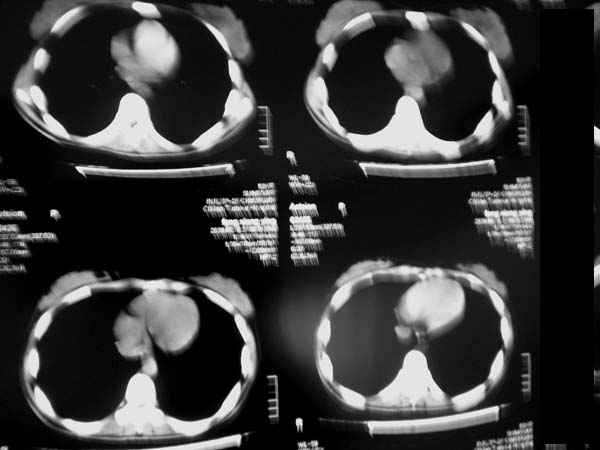

标题: CT13486:F 17Y 咳嗽 咳痰数日请会诊 [打印本页]

标题: CT13486:F 17Y 咳嗽 咳痰数日请会诊

白细胞9600不发烧

考虑右下结核球

右肺下叶结核灶

右下肺背段病灶,考虑结核与炎症鉴别,请进一步检查.

考虑结核球,建议治疗后复查

结核与肿瘤同时考虑

右下肺外基段病灶,考虑炎症,建议治疗后复查,以排外结核

考虑为:右肺下叶外基底段结核球。

结果;痰中找到结核杆菌

痰涂片已找到结核杆菌  将结果告诉大家